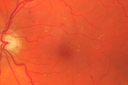

70 year old man with diabetes. OCT scan showed edema vision is 20/25 and the patient is not bothered. The edema did not progress